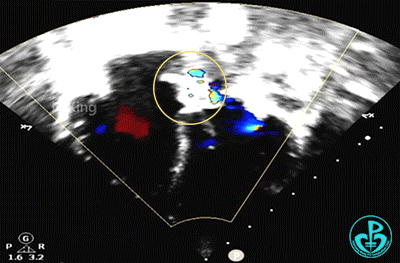

锁定后,主动脉短轴切面显示封堵器呈Y字型抱住主动脉根部。

主动脉短轴切面显示封堵器呈Y字型抱住主动脉根部,夹持稳定。

封堵器形态良好,未见分流,封堵成功。